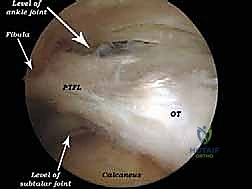

الخطوة 3: الاستكشاف البانورامي (Diagnostic Arthroscopy)

يتم إدخال كاميرا المنظار عالية الدقة (4K) عبر أحد المداخل، بينما تُستخدم الأدوات الجراحية الدقيقة في المدخل الآخر. تتيح الكاميرا للدكتور هطيف رؤية الهياكل الداخلية مكبرة عشرات المرات على شاشة عملاقة، مما يسمح بتقييم دقيق للمفاصل، الأوتار، والأربطة.

* استئصال العظم الزائد (Os Trigonum Excision): يتم فصل العظم الزائد بحذر عن الأنسجة المحيطة واستخراجه بالكامل، مما يزيل سبب الانحشار والألم فوراً.

* تحرير وتنظيف وتر (FHL): إذا كان الوتر ملتهباً ومحاصراً، يتم قطع سقف النفق الليفي لتحريره، وإزالة الأنسجة الملتهبة (Tenosynovectomy) لضمان انزلاقه بحرية.

* إزالة الأجسام الحرة والنتوءات العظمية: يتم التقاط الشظايا العظمية أو الغضروفية وإخراجها، واستخدام أدوات دقيقة (Burr) لتنعيم النتوءات العظمية التي تسبب الاحتكاك.

* معالجة الغضاريف: تنظيف الآفات الغضروفية وتحفيز النخاع العظمي (Microfracture) لتكوين غضروف ليفي جديد.